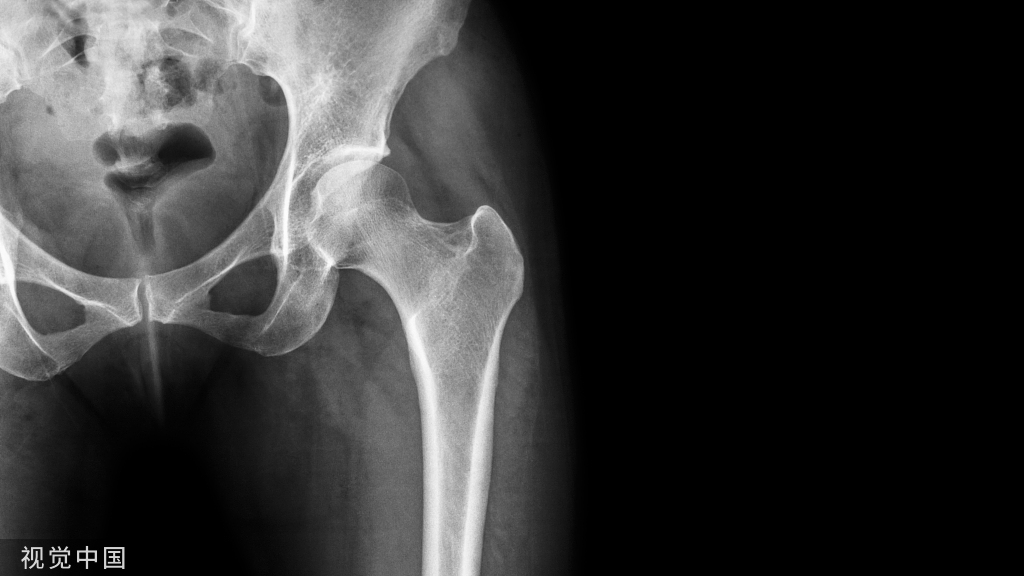

全髋关节置换(THA) 是目前开展最多的人工关节置换。按假体固定方式,分为骨水泥和非骨水泥固定型。

骨水泥能充分填充假体-骨界面的空隙,对提高近、中期假体稳定性有良好的作用,适用于高龄体弱尤其是骨质疏松的患者。但在术中注入骨水泥时,易导致骨水泥植入综合征